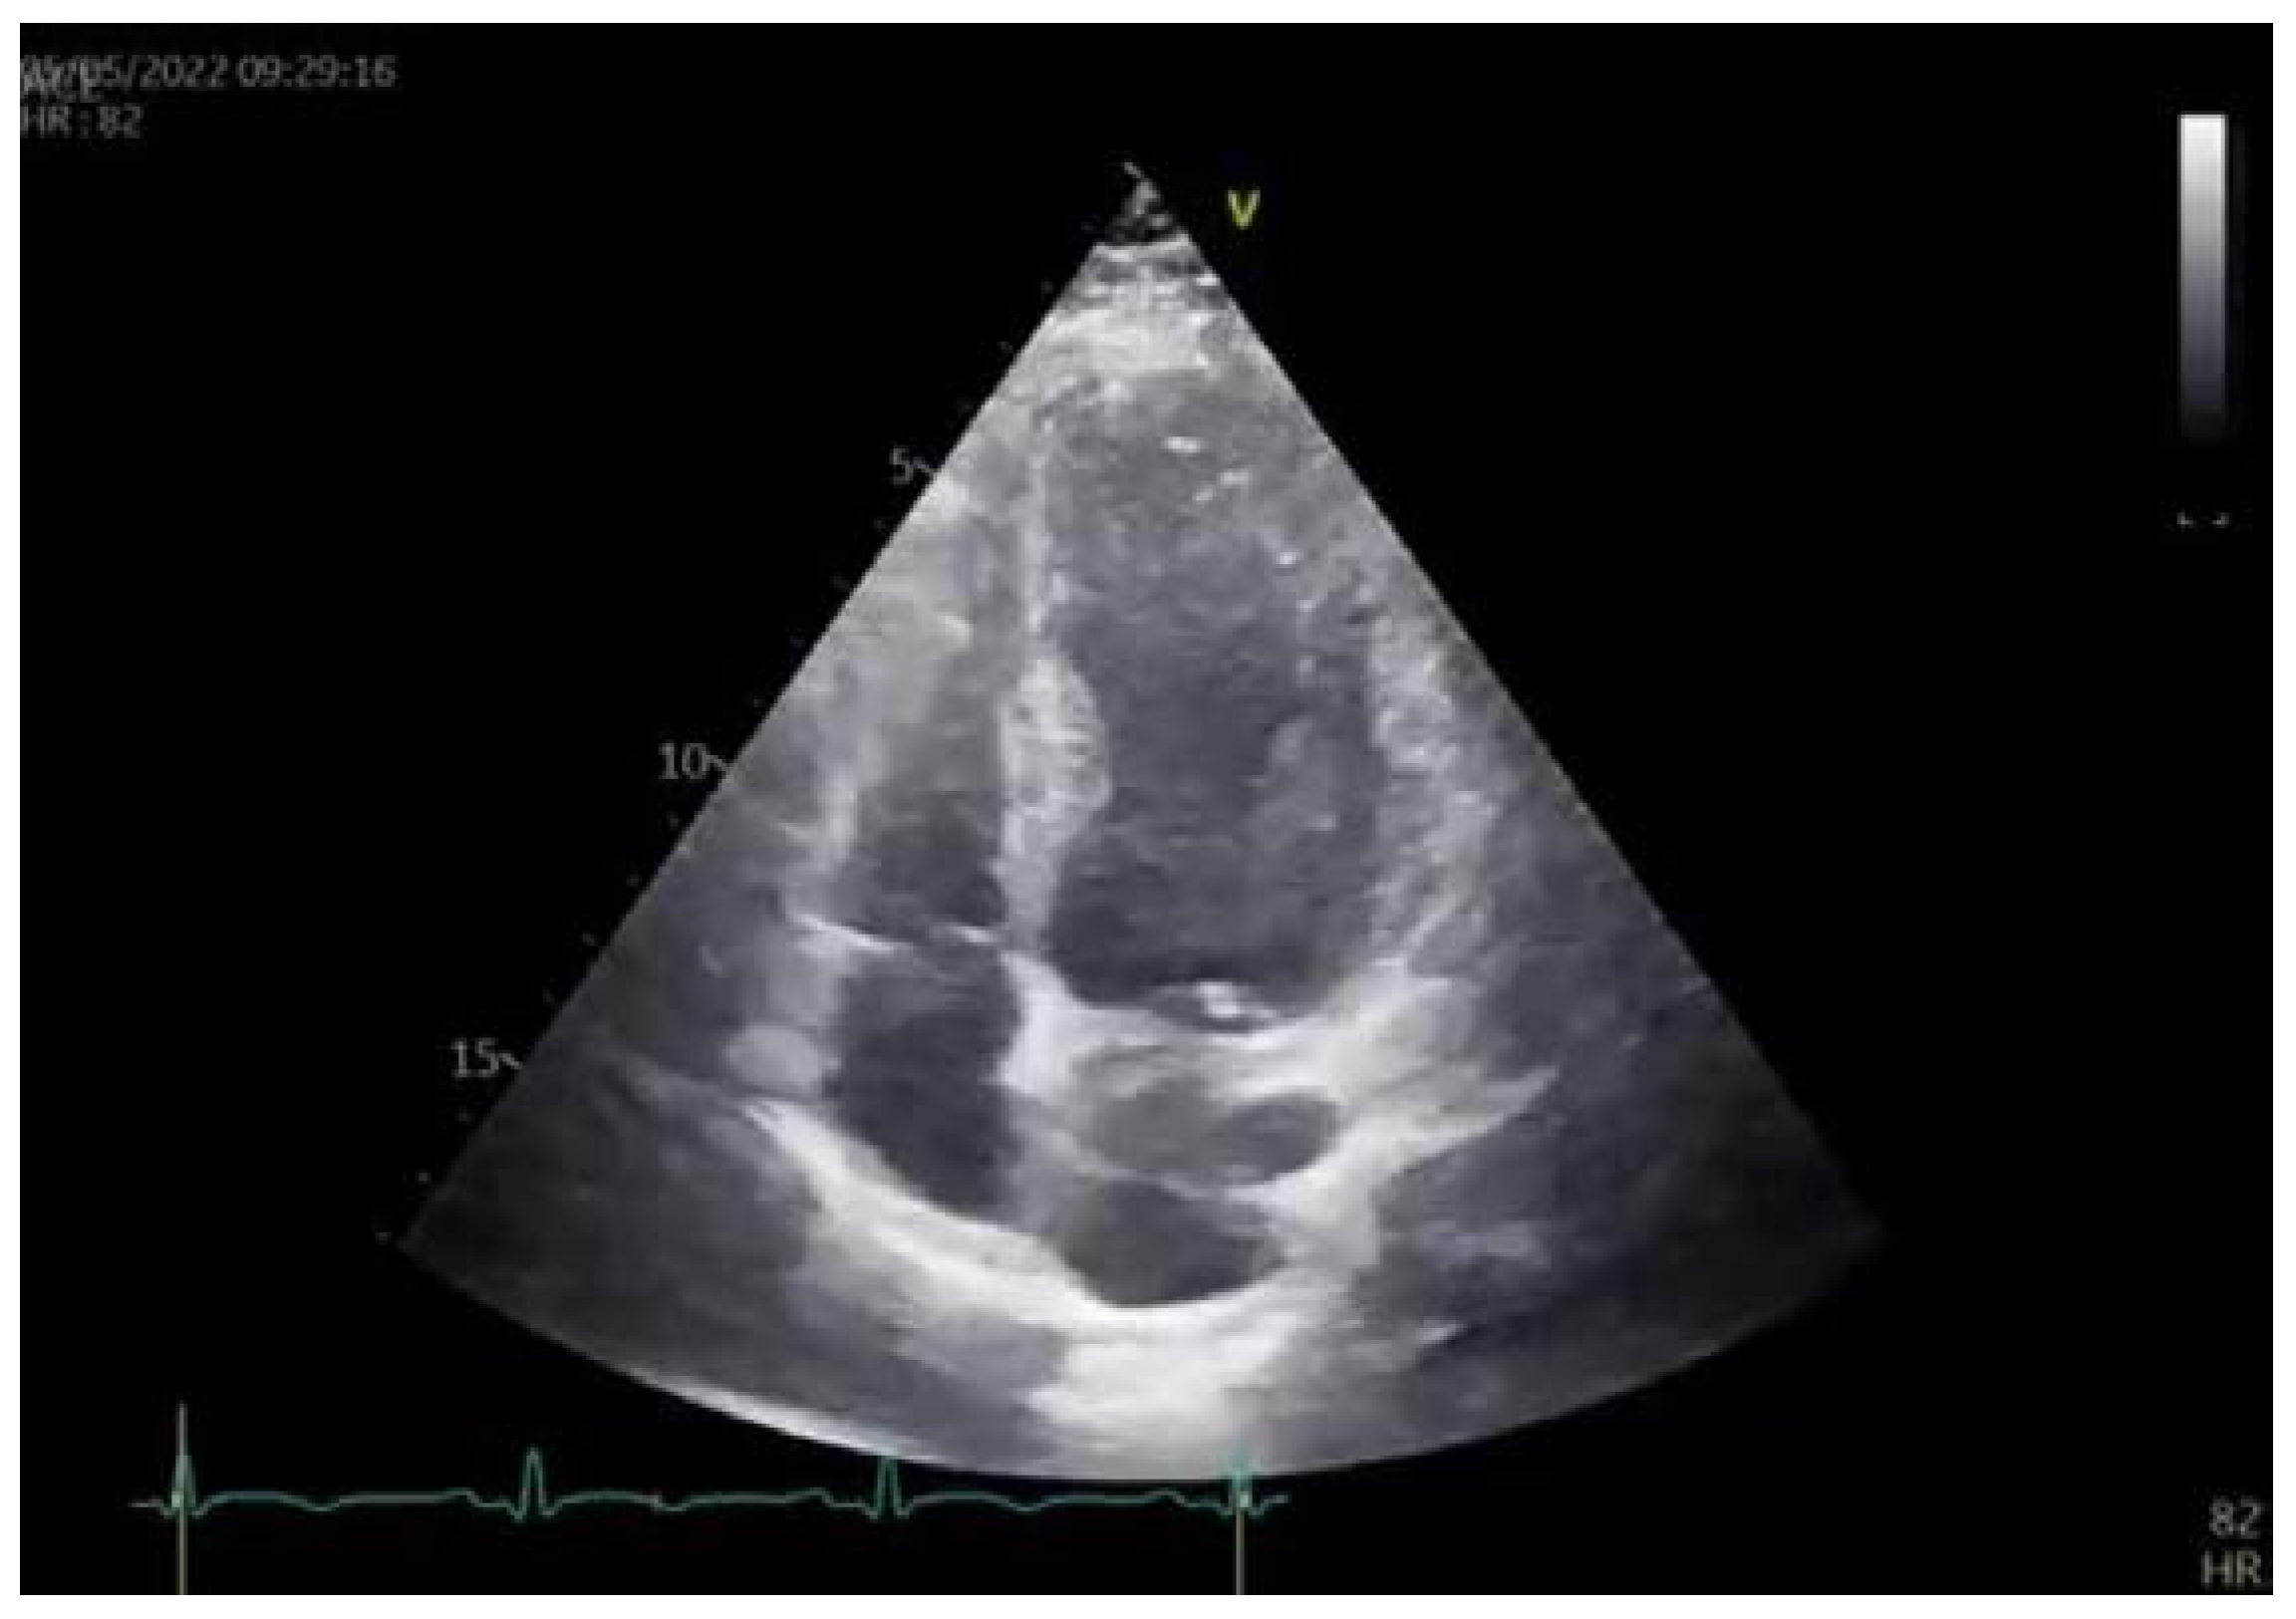

Transthoracic 2D echocardiography showed akinesia of the apical segments of all walls and there was akinesia in practically one-half of the left ventricle (LV). However, the thicknesses of akinetic walls were preserved. Left ventricle ejection fraction (LVEF) was 39%. The echocardiography exam is presented in Videos S3 and S4. Global longitudinal strain (GLS) was −9.7%. Apical segments of LV, assessed by 2D strain echocardiography, were blue-colored in the bull’s eye plot, which was a sign that these segments had completely impaired strain movements, while medial segments of LV had reduced strain movements. Basal segments of LV had good strain movement. Several routine blood and biochemical tests were conducted which showed the following values of two peaks of cardio-specific enzymes on the second and fifth days. Hormonal thyroid status was normal.